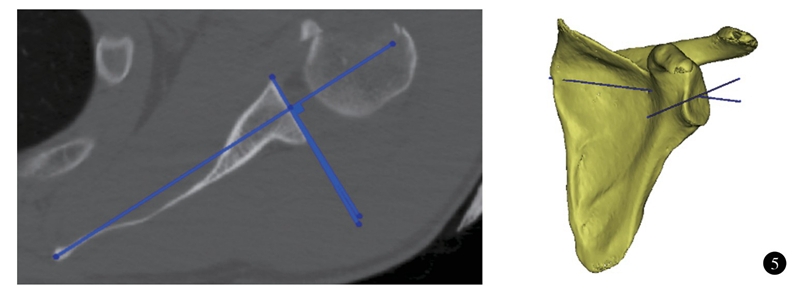

测量肩胛盂前后方向上的倾斜有多种方法。传统二维测量方法是获取患者的二维CT数据,做肩胛骨最内侧的点至肩胛盂中心的连线(friedman线),同时做肩胛盂前缘和后缘的连线(中关节线);中关节线和Friedman线垂线之间的夹角即为肩胛盂前后方向的倾斜角度(图5)。根据成角的方向,又分为前倾(anteversion)和后倾(retroversion)。这种测量方法被认为是测量肩胛盂前后方向的倾斜的金标准。但它没有设立坐标系,不是三维立体测量;肩胛骨的方向、冠状位或矢状位的旋转会影响测量的精度。最新文献建议应使用三维CT测量肩胛盂前后方向的倾斜。Kwon等以肩胛体最低点、肩胛盂中心和肩胛骨最内侧三点建立坐标系,并参考Friedman法测量肩胛盂前后倾(图5),发现三维CT能更精确评估测量肩胛盂前后方向的倾斜,具有更佳的可靠性。国外文献报道,正常人群三维CT测量肩胛盂前后方向的倾斜均值﹣4.5~2°;男女对比并未发现性别差异。汪华清等选取肩胛盂前后缘中点至肩胛骨内侧缘中点的连线作为参考线,测量了国人肩胛盂在前后方向上的倾斜,所得结果为(﹣0.03±4.66)°;其中男性为(1.20±4.87)°,趋于前倾;女性为(﹣1.84±3. 71)°,趋于后倾。与西方研究结果不同,男女性之间比较差异有统计学意义。

图5 二维及三维CT测量肩胛盂前后方向的倾斜角度示意图。肩胛盂中心至肩胛骨内侧连线的垂线与肩胛盂前后缘之间的夹角;图中三维CT测量关节盂前倾角为0°